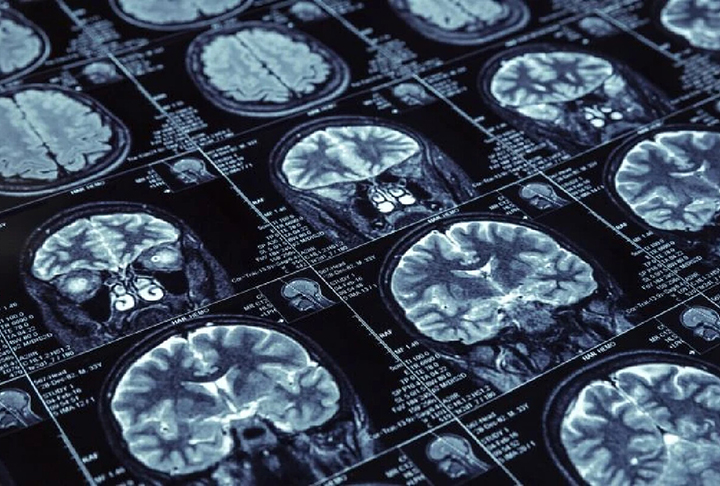

Mundo em alerta sobre Mal de Alzheimer: em 2050, doença deve afetar 139 milhões de pessoas